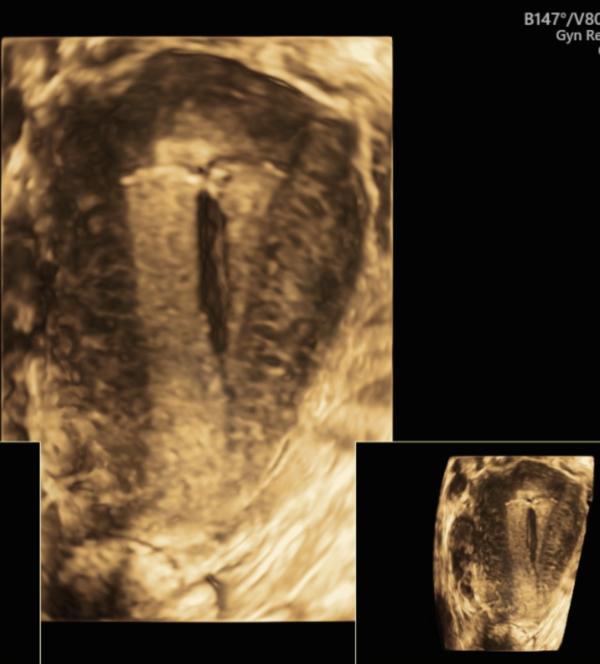

Как красиво встала Мирена в маточку 😍

Вчера установили ее пациентке , с гиперплазией эндометрия .

И мы пока его не установили , так как вот случилось такое осложнение ановуляций в виде гиперплазии эндометрия. И это нужно теперь лечить. Мирена минимум на 6 месяцев , желательно дольше .